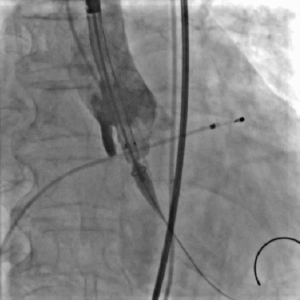

冠脉造影

LAD可见:近段70%-80%弥漫性狭窄,远段75%局限性狭窄,向右冠发出极丰富倒枝循环

LCX远段闭塞

右冠中段闭塞

冠脉造影提示患者存在严重冠脉病变,结合病史,缺血性心肌病诊断明确;

CAG后即刻出现血压下降、心率增快,考虑循环崩溃,因此需立即解决重度主动脉瓣狭窄

球囊扩张

瓣膜定位